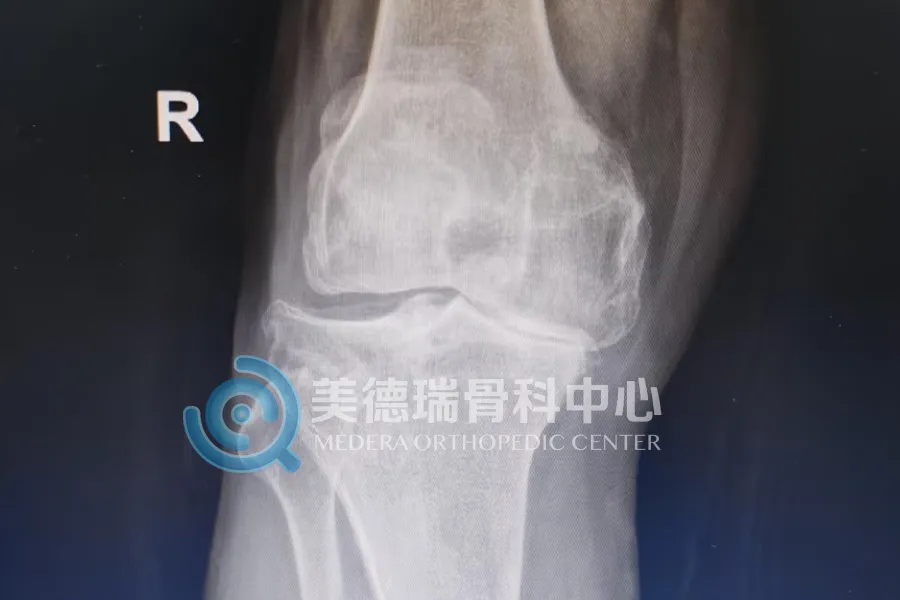

这些患者普遍有一个共同特点,就是病程长、疼痛重、走路越来越困难,日常生活已经受到明显影响。随着关节持续退变,不少患者逐渐出现膝关节变形、行走困难,上下楼和日常活动都受到影响。

重度膝关节骨关节炎发展到后期,关节磨损明显,疼痛会反复加重,腿形和力线也会随之改变。到了这个阶段,全膝关节表面置换术是较为成熟、有效的治疗方式。手术的目标也很明确,就是减轻疼痛,纠正畸形,恢复负重和行走能力。

近期接受治疗的一位68岁患者就是一个典型的例子。双膝疼痛已持续8年,近1个月明显加重,同时合并高血压和糖尿病。入院检查显示,其膝关节退变已较为严重,关节间隙明显变窄,力线也已发生改变,日常行走受到明显影响。经过术前评估和围手术期准备后,美德瑞骨科中心为其实施了全膝关节置换术。术后复查显示,患肢力线得到纠正;从术后站立和行走情况看,患者恢复平稳,已具备早期下地活动条件。